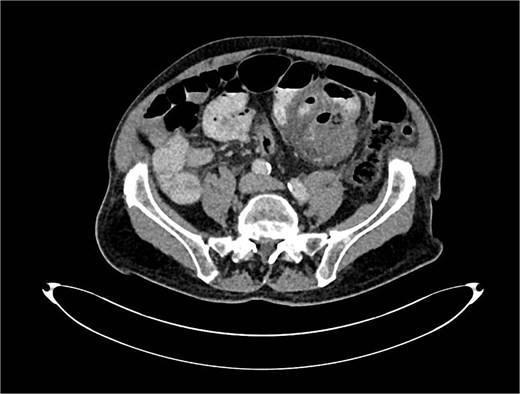

A computed tomography angiography (CTA) of the abdomen was performed, it showed a long segment of the small bowel with wall thickening in the right lower quadrant, accompanied by a inflammatory change in the mesenteric fat with multiple air bubbles, and free fluid in the pelvis, suggestive of hollow organ perforation (Fig. 1). Given the high suspicion of hollow organ perforation and clinical signs of peritonitis, an indication for exploratory laparotomy was established and performed as an emergency procedure. An antibiotic therapy with piperacillin/tazobactam was empirically initiated preoperatively.

CTA showing a long segment of small bowel with inflammatory wall thickening and fat stranding of the mesentery with multiple air bubbles.